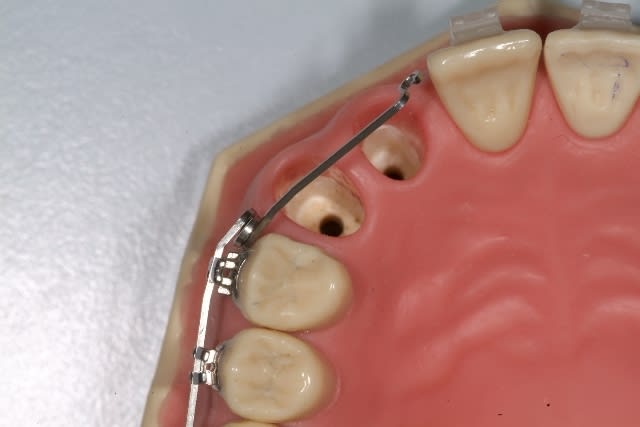

Ne peux-tu imaginer un ressort de type cantilever qui délivre une force légère, contrôlée et d’une plus grande amplitude. ?

Voilà une alternative avec un dispositif qui permet le réglage de la force en module et direction. Je l'utiliserais avec un double tube sur 16 , avec le ressort dans le tube gingival et un arc complet dans l'autre.

Effets indésirables : extrusion et mésioversion coronaire de 16 mais vu la force, négligeable a à mon avis( mini vis si doutes). Si tu ne veux pas engager la 14, le ressort prendrait 16 et 15.

L'espace entre 14 et 11 est plus reduit chez ton patient que sur mon modèle.

Avec la première solution dont j'avais parlé précédement, je mets un up-righting-spring(TP ortho) pour envoyer la racine de 14 en distal.

le ressort dont tu parles s'appelle un descendeur canin. A mon avis, et du point de vu biomecanique, l'attacher sur la 4 ou sur la 5 va engendrer une force reactionnelle d'ingression de la premolaire. Donc il faut mieux avoir un double tube sur la molaire, passer un fil rigide dans le tube occlusal sans engager la 4, si l'on veut la laisser libre, et dans le tube gimgival on fait passer le ressort. Ceci donne un brs de levier plus long et plus efficace, et la 6 stabilisee n'aura pas de mouvement parasite. On peut utiliser un dispositif palatin type ATP pour renforcer l'ancrage de la molaire et on peut faire le ressort en TMA .016 X .022 pour plus de souplesse. Le reste tout va bien.

Exact, il y a tendance à l'ingression de la 14 sur le dispositif qui est en photo.

C'était juste pour illustrer le type de ressort.

Je le mettrais effectivement en place comme tu dis;je n'engage pas le ressort dans la gorge des attaches des PM qui recoivent l'arc de base;juste une ptite ligature pour que ca ne se promène pas.